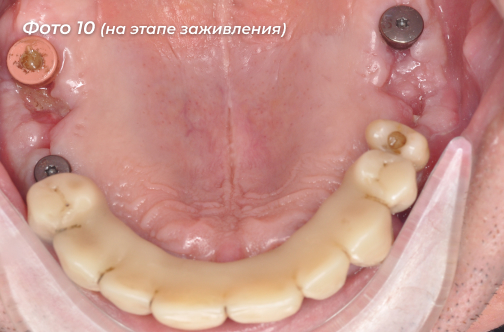

Был изготовлен и установлен временный протез с временной опорой на свои оставшиеся зубы (Фото 9, 10).